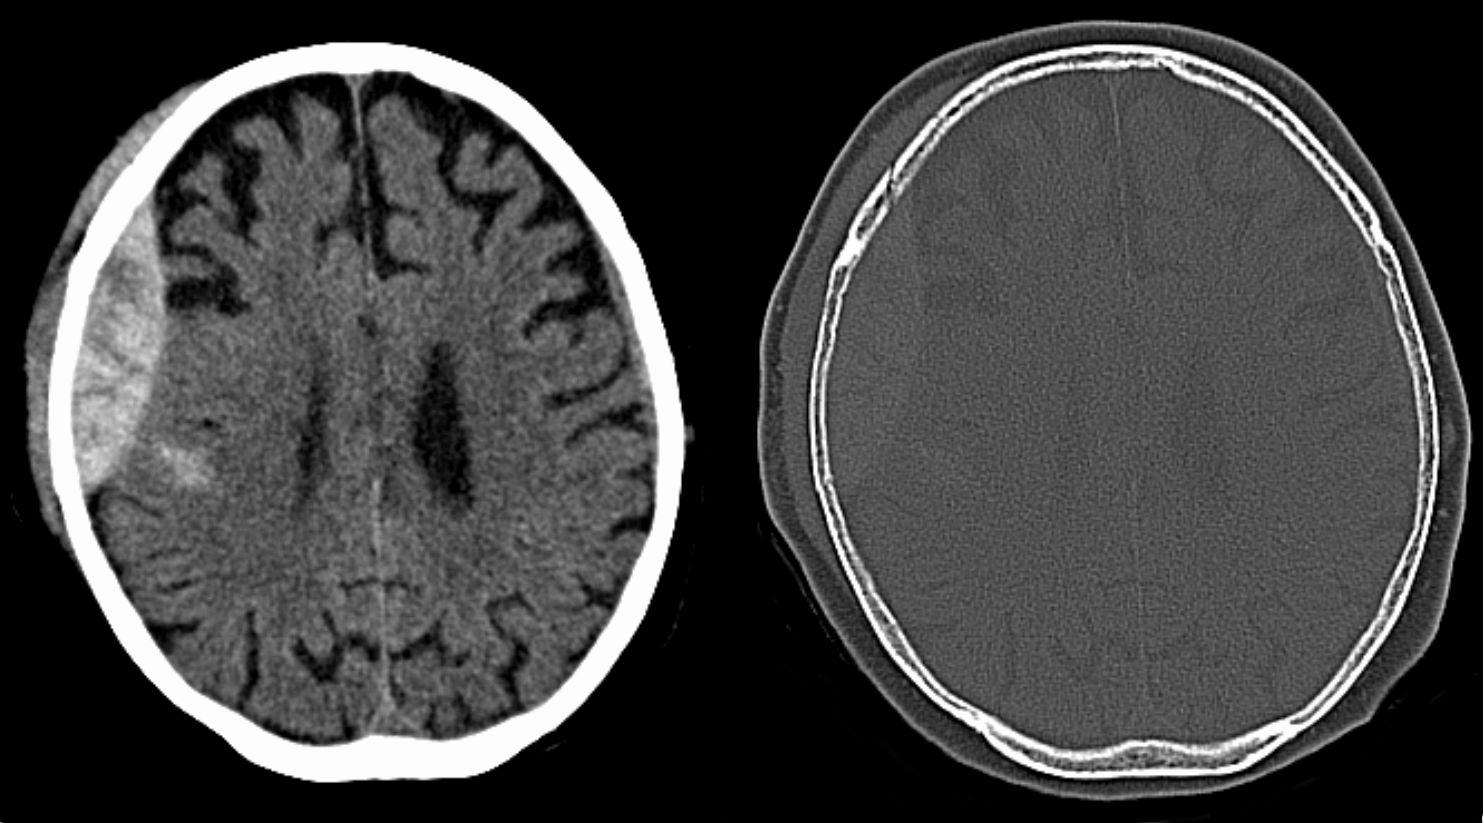

硬腦膜上出血

硬腦膜是腦膜最外層,硬腦膜上出血即腦膜與頭骨之間出血。患者或有「清醒期」,即腦部有出血但人仍清醒、舉止正常,但持續出血並壓迫到腦部組織,就可能突然失去意識。如出血量大,須手術移除血塊。

硬腦膜下出血

即血液積聚於硬腦膜與蜘蛛網膜之間,成因多為外傷撞擊,而扯斷了腦膜的血管。患者或突然出現認知障礙、反應遲緩、言語不清、行路不穩。只要打開硬腦膜引流積血便可回復正常,但頭骨或須待腦壓降低後才可放回。